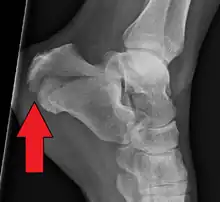

X-ray of a fractured calcaneus

It usually occurs when a person lands on their feet following a fall from a height or during a motor vehicle collision.[2][1] Diagnosis is suspected based on symptoms and confirmed by X-rays or CT scanning.[1]